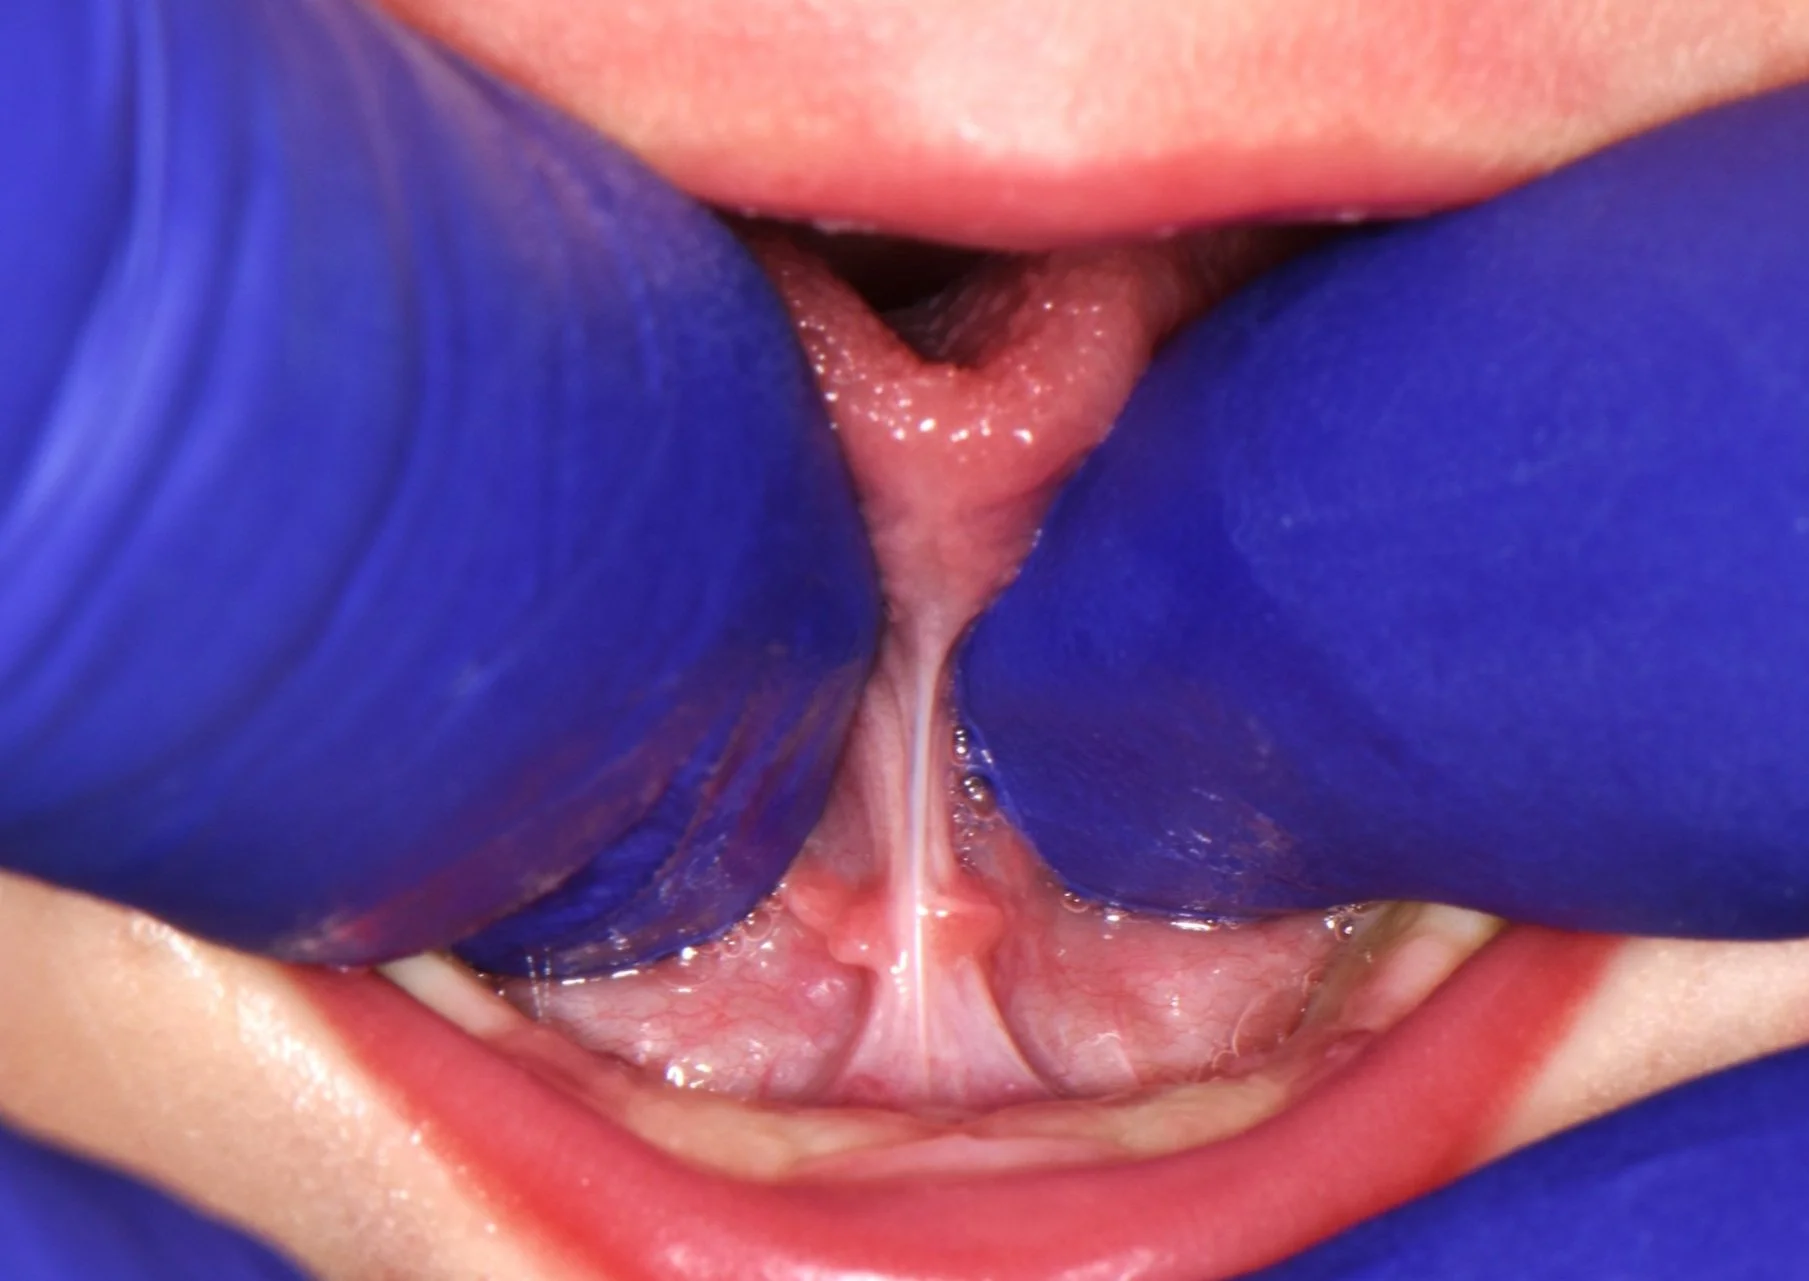

Photo of Tooth Socket After Extraction, Before Bone Graft

The socket after gentle extraction.

A clear picture of the collagen plug over the top of the bone graft. You can see two of the white sutures as well.